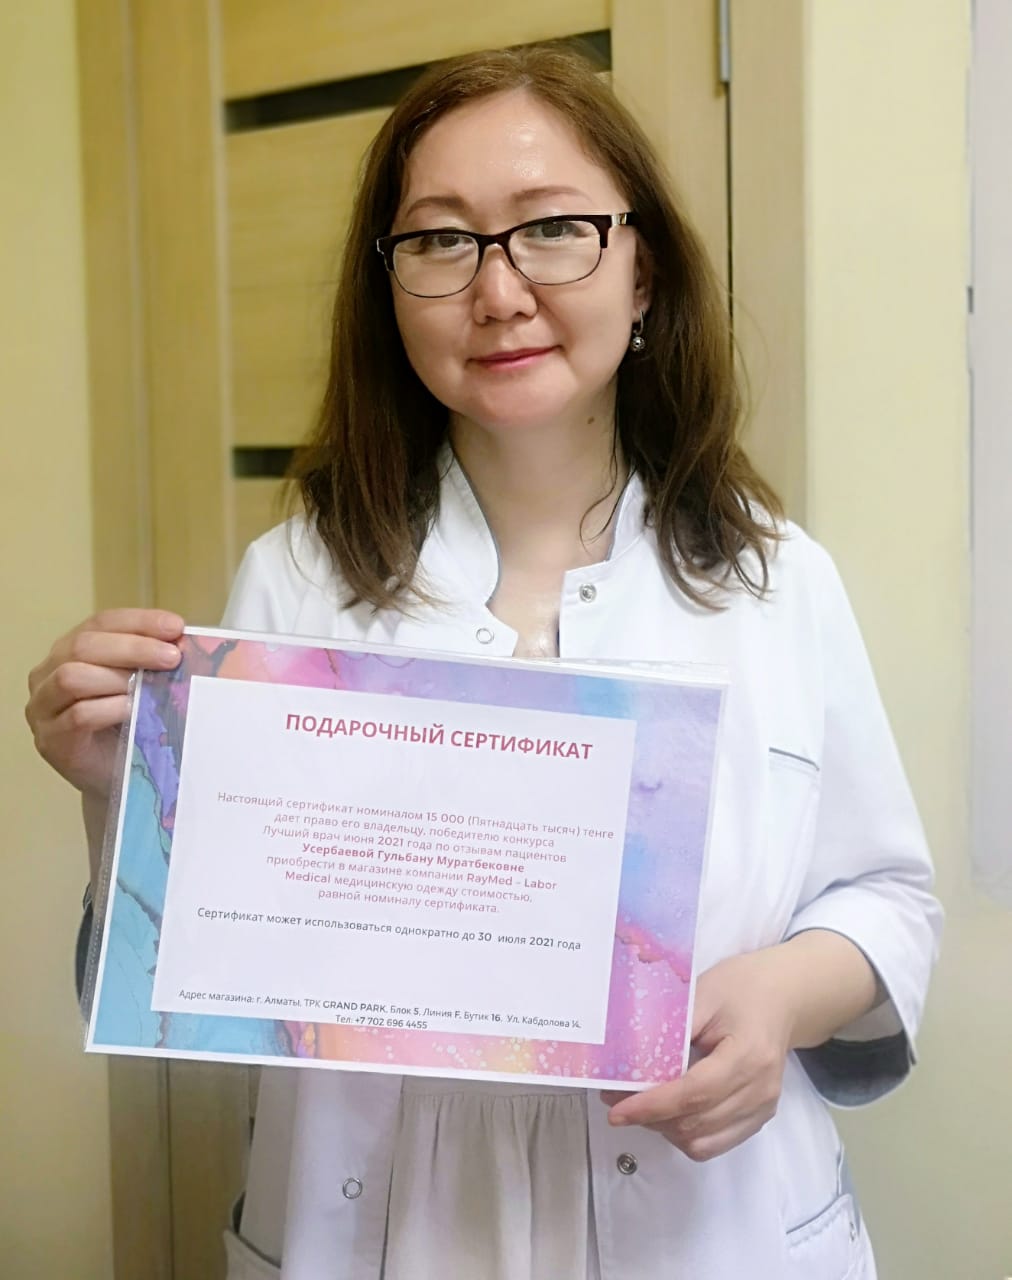

TopDoc.kz қолданушылары бірінші жаз айының ең үздік дәрігері ретінде 17 жылдық жұмыс өтілі бар ревматолог Усербаева Гульбану Муратбековнаны таңдады. Дәрігер Гульбану Муратбековна, медициналық ғылымдар кандидаты, дәнекер тіндерінің ауруларын – буындарды, қан тамырларын, теріні қолдан емдейді. Артроз және артрит, подагра, остеопороз, гранулематоз, васкулит және басқа да аурулар бойынша көмектеседі, Гульбану Усербаева доцент ретінде өз саласындағы медициналық ғылымның соңғы жетістіктерін әрдайым біліп отырады.

Дәстүр бойынша, демеуші labormedical.kz-тің сыйлықтарын табыс етіп, біз доктор Усербаеваға остеоартроз/остеоартрит туралы ең өзекті сұрақтарды қойдық. Бұл ауру қарт адамдарда мүгедектіктің негізгі себебі болып табылады, шамамен 7% ғаламшар халқын қамтиды, бұл 500 миллионнан астам адамды құрайды.

TopDoc.kz сервисі аптаның ең үздік дәрігері байқауының серіктесі RayMed компаниясына – Labor Medical түрік өндірушісінің медициналық киімін жеткізушіге алғысын білдіреді. Дәрігерлер өмірінің көп бөлігін медициналық униформада өткізеді, сондықтан оларға күні бойы ыңғайлы болу өте маңызды. Labor Medical медициналық киімі дәрігерлердің барлық талаптарына жауап береді, өйткені қолданылатын мата бірегей – ол тыныс алады, мыжылмайды, оңай жуылады, оңай үтіктеледі, түсі мен құрылымын ұзақ сақтайды, ал жиынтықтар мен халаттардың модельдері қозғалыстарды шектемейді, ыңғайлы, практикалық және өте стильді!